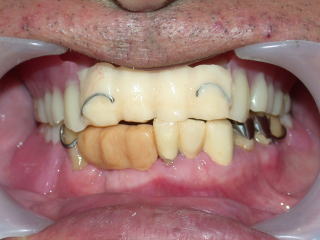

平成29年2月6日 下顎のみクラスプレスデンチャー装着しました。

上の前歯は最近抜けて旧義歯に増歯しています。

下の前歯は数年前に抜けて旧義歯に増歯したままです。

今回、上下義歯とも綺麗に治療したい、とのことでした。